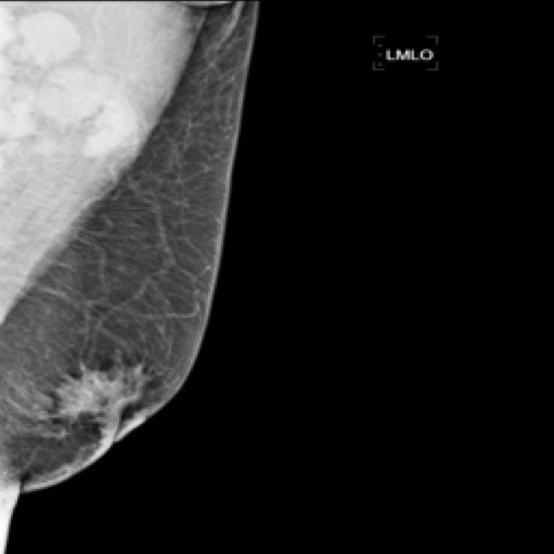

Fig. 1 illustrates the workflow of radiologists in assessing suspected breast lesions. This process begins with the radiologist drawing on both the consensus in radiology and their experience. They observe the lesion from various perspectives, focusing on its manifestations such as shape, contour, and density. The findings are then documented in mammography reports. This workflow encompasses three key elements: 1) Mammography Images providing visual information. However, the disease-related features in these images are often complex and subtle, making accurate interpretation challenging. 2) Manifestations representing the expert knowledge in analyzing breast lesions, which are rich in dense, semi-semantic information. 3) Mammography Reports standing for the linguistic summaries of the radiologist’s observations with containing highly sparse and abstract semantic information. The reports encapsulate the radiologist’s final interpretation and conclusions based on the visual and manifestation data.

Mammography Imaging. In radiological examinations, multiple views are captured to thoroughly represent lesions. For mammography, these typically include four views: left mediolateral oblique (LMLO), left craniocaudal (LCC), right mediolateral oblique (RMLO), and right craniocaudal (RCC). To ensure dataset completeness and versatility for various tasks, we retained all views in their original form, irrespective of the presence breast lumps. However, views without breast lumps are not involved in this study.